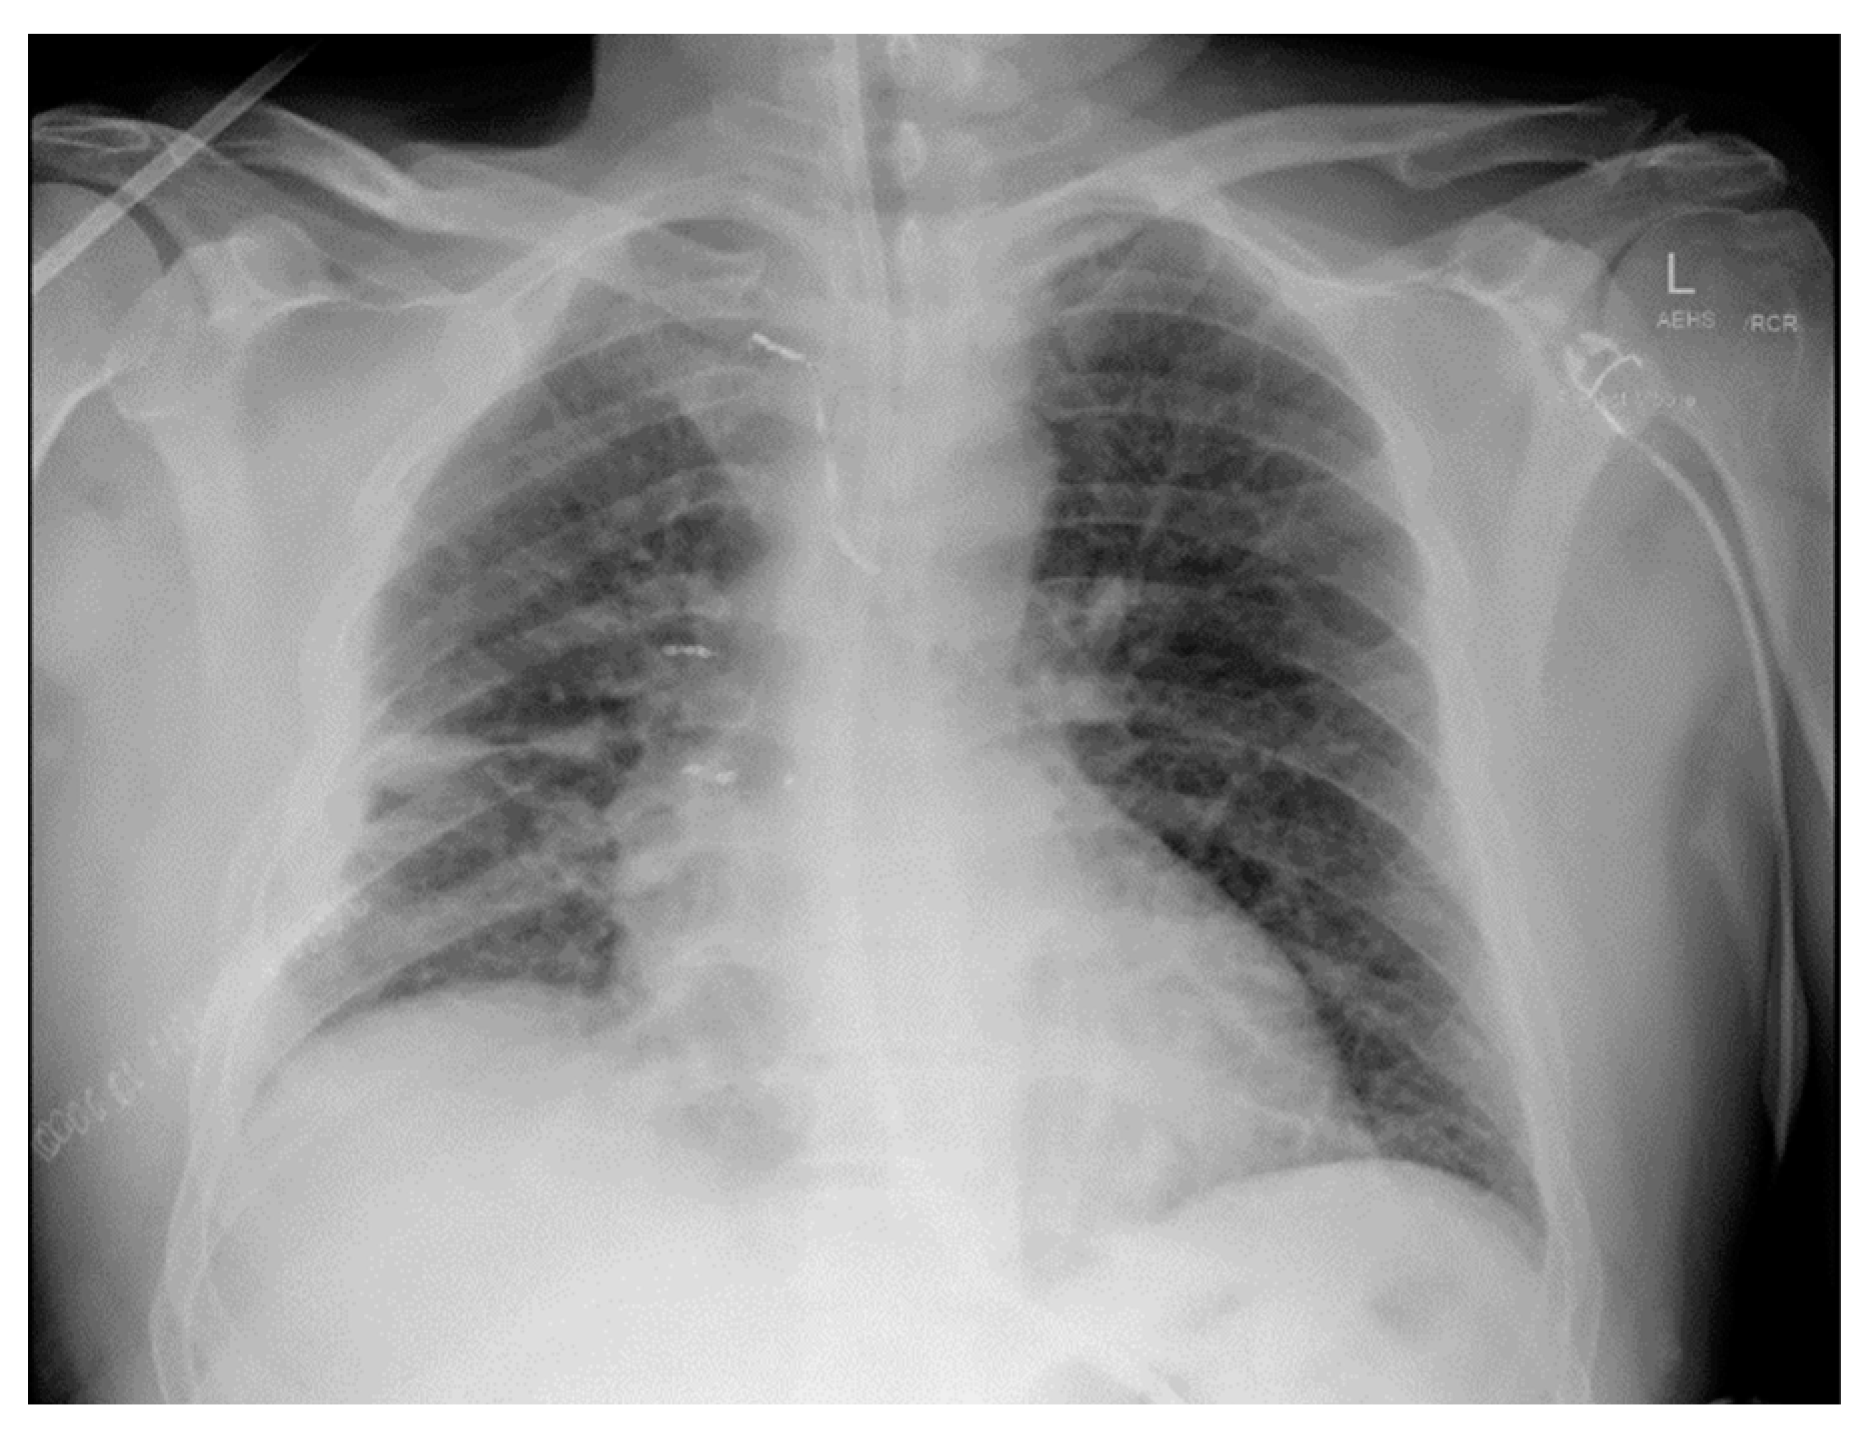

Arrival at the tertiary hospital happened two hours later, where he started to deteriorate at a faster pace. He remained afebrile, with a blood pressure of 97/49 mmHg, pulse rate of 112 bpm, and tachypneic at 26 respirations per minute with 92% saturation on 15 L of oxygen from a non-rebreather mask. The shock index was 1.2 at this time. A quick point-of-care venous blood gas showed a high anion gap metabolic acidosis with a raised lactate of 3.5. At this point, he entered a hemorrhagic shock along with a respiratory compromise secondary to the expanding hemothorax causing an external restrictive effect on his lung parenchyma. He was quickly sent for a repeat CT chest study without contrast (Figure 3) and was given one unit of packed red blood cells along with 2 g of fibrinogen concentrate. Shortly after, he was being sedated for a selective angiography of his right intercostal arteries and embolization of areas of bleeding.

Figure 3. Multiphase CT scan without contrast, arterial and delayed phases, progressing from superior to inferior, compared to previous CT. Increasing size of large right extra-pleural hematoma with multiple sites of active bleeding from intercostal arteries. Moderate-sized right hemothorax seemingly enlarging. Superior mediastinal and right chest wall hematoma.